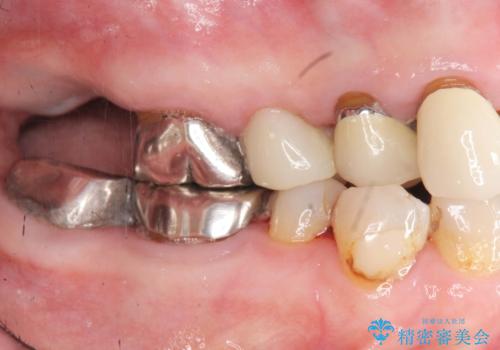

- 見た目の悪い銀歯や虫歯、歯の欠損、全体的な治療を希望されて来院されました。

インプラント治療や根管治療・セラミック治療を総合的に考えた精度の高い治療を計画し、しっかり噛めるようになるのはもちろん長期的な予後や審美性の向上を考えた全顎的な治療を実践していきます。